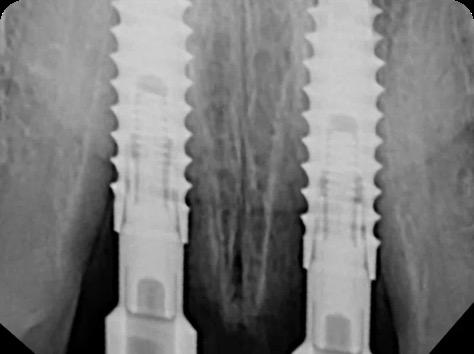

BioHorizons has introduced a new implant system that combines the advanced thread design of the Tapered Pro with the precision and stability of the Conelog conical connection. This integration delivers enhanced surgical handling, improved primary stability, and long-term biological benefits, supporting better patient outcomes in both aesthetic and functional zones.

This case was performed by Dr Homa Zadeh, DDS, PhD, a respected leader in periodontology and implant dentistry. Dr Zadeh’s approach emphasizes biologically driven protocols and evidence-based techniques, making this case a strong example of clinical excellence using the Tapered Pro Conical system. It involves the replacement of two front anterior teeth after they fractured off and the full restoration process.

Fig 2. Intraoral radiograph indicating tooth structural loss extent.

Fig 9. Periapical radiograph for verification of proper seating of the scanbodies.

Fig 13. Radiograph of implants, grafts and Provisionals.